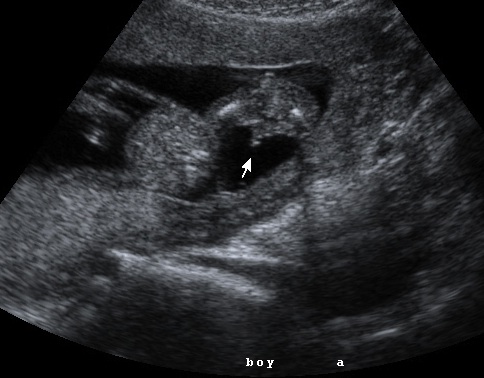

{ our son }